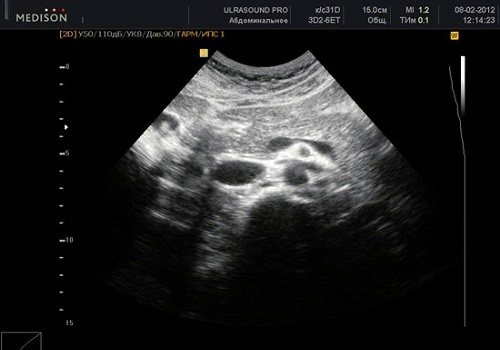

Рак на УЗИ выглядит в виде объёмного образования в структуре органа. Оно может выявиться в зоне головки, тела или хвоста. На УЗИ визуализируется размер, форма и плотность опухоли. При раке головки отмечают её увеличение. Она приобретает округлую форму. Выявляют распространение злокачественного процесса на соседние органы, прорастание опухоли в близлежащие сосуды, появление метастатических очагов в лимфатических узлах.

Опухоль на мониторе аппарата УЗИ просматривается в качестве объемного новообразования, имеющая неправильную форму и неровные края. Наблюдается изменение тканей поджелудочной железы низкой эхогенности. Образование неоднородной структуры. Нередко возникают сложности дифференциации образования от псевдотуморозной формы панкреатита, потому требуется тщательное исследование панкреатического канала. При болезни основной панкреатический проток выглядит расширенным, на своем протяжении его диаметр неравномерный. Когда есть рак, канал расширяется только ниже опухоли.

При проведении УЗИ можно увидеть характерный эхопризнак ракового новообразования — значительное увеличение отдельной части железы или выбухание ее контура. В 50-80% случаев в онкозаболевание вовлекается головка ПЖ. Даже опухоль незначительных размеров является хорошо видимой в головном конце на УЗИ. Это связано со следующими причинами:

При раке ПЖ изменяются контуры органа: они становятся нечеткими, но, в отличие от хронического панкреатита, не имеют неровностей или зазубрин. В месте расположения опухоли визуализируются выпуклости, которые проникают в окружающую клетчатку в виде языков. Все это подробно описывается в заключении УЗИ.

В основном раковое образование ПЖ является гипоэхогенным, в нем не содержится внутренних эхоструктур. Но бывают опухоли с диффузно определяющимися эхосигналами или высокоинтенсивными эхосигналами в центре узла при отсутствии их на периферии опухоли. Граница между измененной опухолью и остальной тканью железы может быть нечеткой, но приблизительно видна всегда за счет разности в эхогенности нормальной и патологической ткани. Несмотря на схожесть структуры ткани образования (особенно если в ней отсутствуют участки структур с повышенной плотностью) с кистой, УЗИ с помощью эффекта дистального усиления дает возможность отдифференцировать злокачественный очаг от жидкостного образования.

При наличии опухоли в головке ПЖ анализируются данные расширенного вирсунгова протока: при раке выявляются ровные и неуплотненные стенки, в отличие от их изменений при хроническом панкреатите. Если диаметр главного выводного протока равен примерно половине толщины самой ПЖ, это является одним из признаков злокачественного процесса.

На УЗИ можно диагностировать сдавление и смещение проходящих рядом сосудов – нижней полой и брыжеечной вены. Это наблюдается и при хроническом панкреатите, и при опухоли, но в случае злокачественного образования выражено значительнее. При локализации опухоли в головной части ПЖ происходит смещение верхней брыжеечной вены в вентральном направлении, а при достижении узлом больших размеров сдвигается и сама головка.